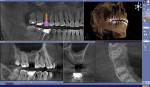

Sirona’s GALILEOS Implant software is a 3-dimensional (3-D) program that allows users to plan implant procedures in a very short period of time. GALILEOS offers a high degree of safety because it allows clinicians to visualize the patient’s nerve canal and bones in three dimensions, enabling precise planning and procedures. Smithson believes that the integration of CAD/CAM technology into implant planning has made Sirona’s system stand out in a crowded marketplace. “Integrating CAD/CAM into implant planning allows the clinician to do a full evaluation and a full treatment plan prior to even sitting down with the patient and doing the consultation, let alone prior to the treatment itself,” explains Smithson.

Sirona’s CEREC® CAD/CAM system also aids clinicians in their implant treatment planning. With CEREC, the clinician is able to execute the implant procedure in fewer visits to the dental office. Smithson elaborates, “Clinicians are able to make a surgical guide with Sirona’s CEREC CAD/CAM system, which means they can perform the implant placement in one visit to the dental office. The system can even mill a crown for the patient while he or she is in the office.” In addition to shortening the time required for implant surgery, implant surgical guides are highly accurate, and ensure that the implant is placed correctly, thus improving case acceptance.